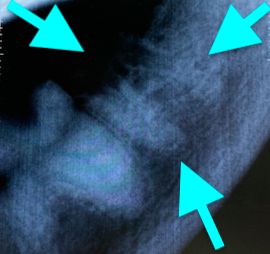

Внутриротовые рентгенограммы всей полости рта являются важным диагностическим инструментом, помогающим выявлять и классифицировать резорбцию зубов. Нередко резорбция, отмеченная на одном зубе, выявляется на таком же зубе симметрично.Существуют два широко используемых метода классификации резорбции зубов у кошек на основании радиографической картины (по стадии и типам). Рентгенологическая картина резорбции зуба варьируется от незначительных рентгенопрозрачных дефектов поверхности зуба в области цементно-эмалевой границы до обширной резорбции замещающего корня, придающей зубу пятнистый или изъеденный молью вид. Планирование лечения также включает рентгенографическую оценку пространства периодонтальной связки.

Классификация по типам рентгенологических проявлений резорбции зубов1 (фото 17):

Тип 1: наблюдается потеря альвеолярной кости, примыкающей к области резорбции зуба, на других участках зуба сохраняется нормальное пространство периодонтальной связки.

Тип 2: потеря пространства периодонтальной связки и цемента зуба из-за сращения корня зуба с альвеолярной костью (дентоальвеолярный анкилоз), резорбирующаяся структура зуба выглядит менее рентгеноконтрастно, чем неповрежденный зуб.

Тип 3: комбинация типов 1 и 2.